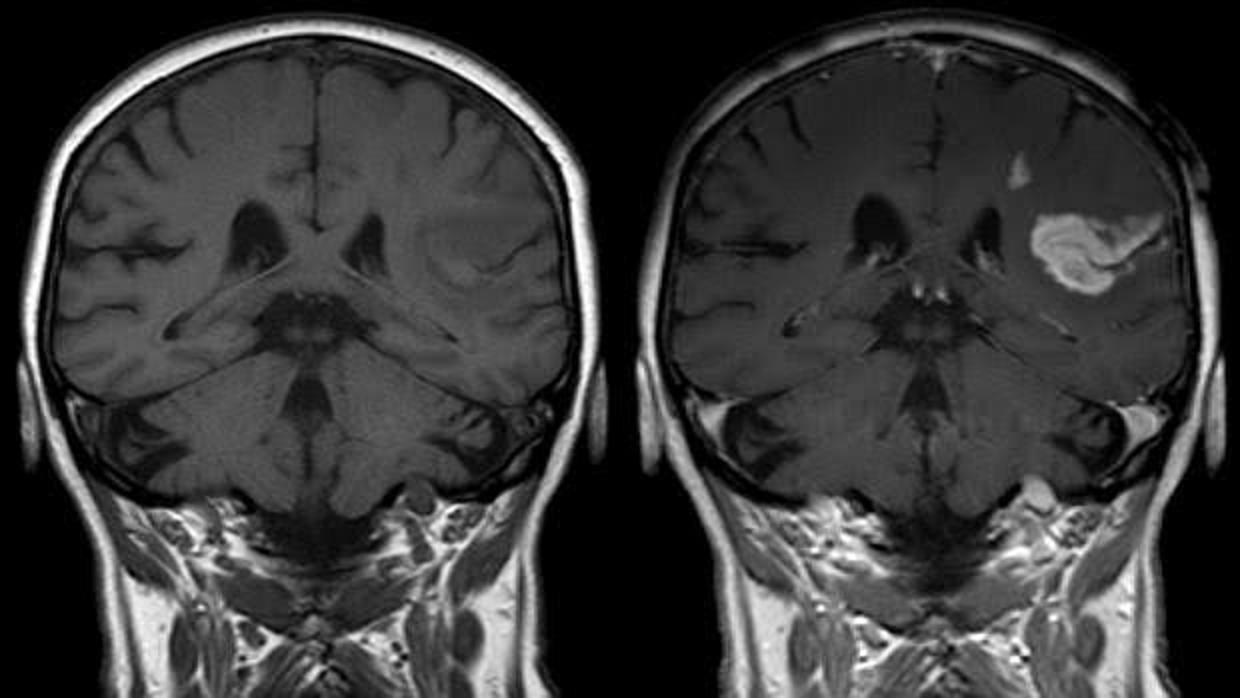

De acuerdo con los datos de la Sociedad Española de Oncología Médica (SEOM), el cáncer es responsable cada año de la muerte de uno de cada cuatro ciudadanos de nuestro país. De hecho, y con 106.034 decesos registrados en 2014, las enfermedades oncológicas constituyen la segunda causa de mortalidad en la población española, estando esta cifra únicamente superada por la atribuida a las patologías cardiovasculares –116.456 decesos en 2014–. Sin embargo, y más allá de su elevada letalidad, es posible que los distintos tipos de cáncer estén contribuyendo al desarrollo de las enfermedades cardiovasculares. Y es que un nuevo estudio llevado a cabo por investigadores del Hospital Universitario de La Princesa en Madrid muestra una significativa asociación entre el cáncer y el accidente cerebrovascular o ictus, sugiriendo que la presencia de un tumor podría llegar a promover la presentación de un ictus isquémico –episodio que, otrora denominado ‘infarto cerebral’, está causado por una disminución u obstrucción del flujo sanguíneo en el cerebro.

En definitiva, y de acuerdo con las evidencias alcanzadas en este estudio, parece existir una clara asociación entre los accidentes cardiovasculares y el cáncer. Más concretamente, que la presencia de un tumor ayuda a promover el desarrollo de un ictus. Pero esta relación, ¿cómo se explica? Pues según apunta Jacobo Rogado, «se ha sugerido que el cáncer es un estado hipercoagulable en el que las células tumorales activan el sistema de coagulación. Esto podría explicar nuestra observación de unos mayores niveles de fibrinógeno en aquellos pacientes diagnosticados de cáncer. Podría ser que el efecto protrombótico del cáncer contribuya a los ictus».